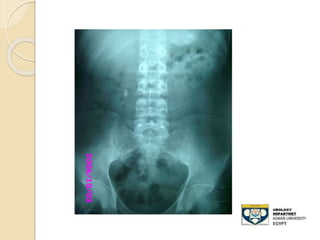

KUB film

 - Advantages:

◦ 80-90% of stones are radio-opaque

◦ Minimal radiation

 Disadvantages:

◦ Radiolucent stone

◦ Easy to miss mid-ureteral stones over the

sacrum

◦ Bowel gas can obscure its efficacy

◦ Cannot differentiate , Stones,Calcified LN

,

◦ Sensitivity: 50-70%

STONE MIDDLE THIRD URETER